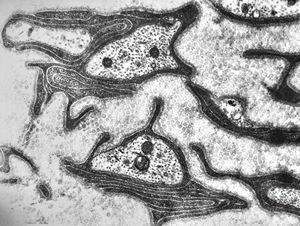

F,25y. | metachromatic leukodystrophy - n. suralis

F,8y. | metachromatic leukodystrophy - n. suralis